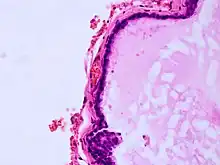

| Histopathology of colloid cyst |

A colloid cyst is a non-malignant tumor in the brain. It consists of a gelatinous material contained within a membrane of epithelial tissue. It is almost always found just posterior to the foramen of Monro in the anterior aspect of the third ventricle, originating from the roof of the ventricle. Because of its location, it can cause obstructive hydrocephalus and increased intracranial pressure. Colloid cysts represent 0.5–1.0% of intracranial tumors.[1]